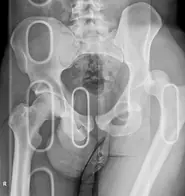

Fracture du bassin